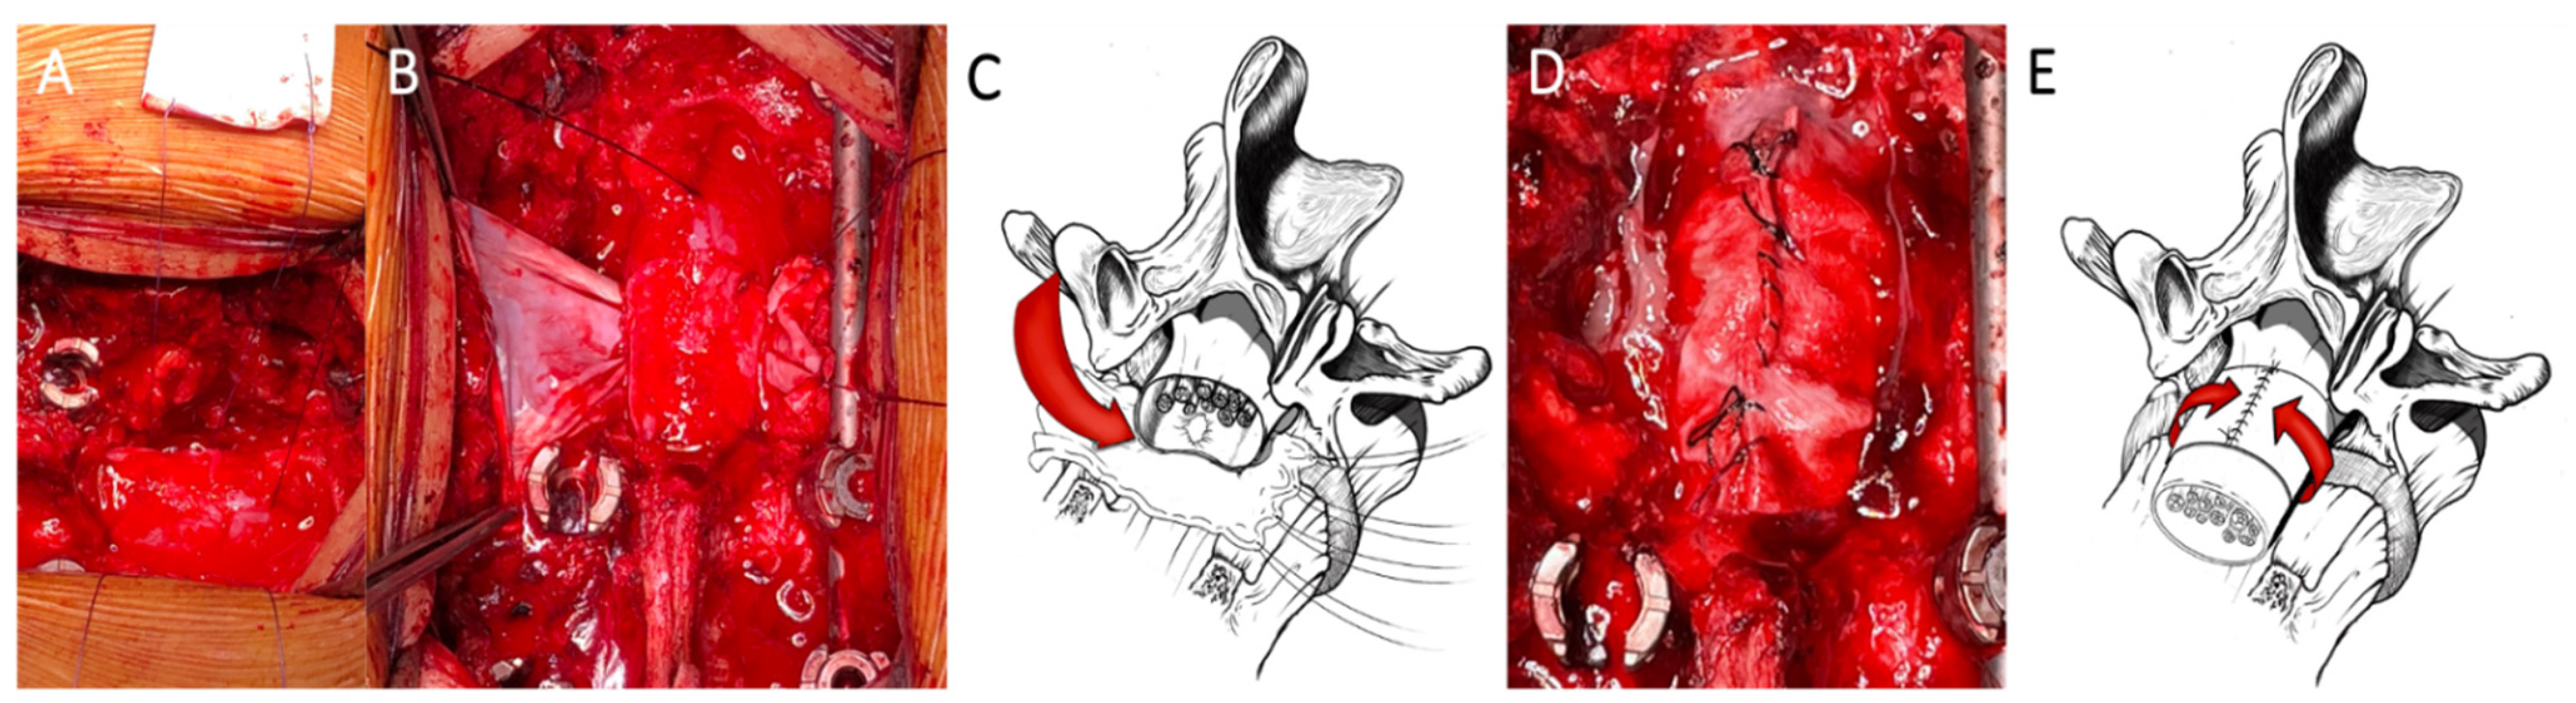

3. Coating Techniques

3.1. Dural Coating

3.2. Dural Coating Straddling Nerve Roots

3.3. Dural Coating with Sutured Fat Graft